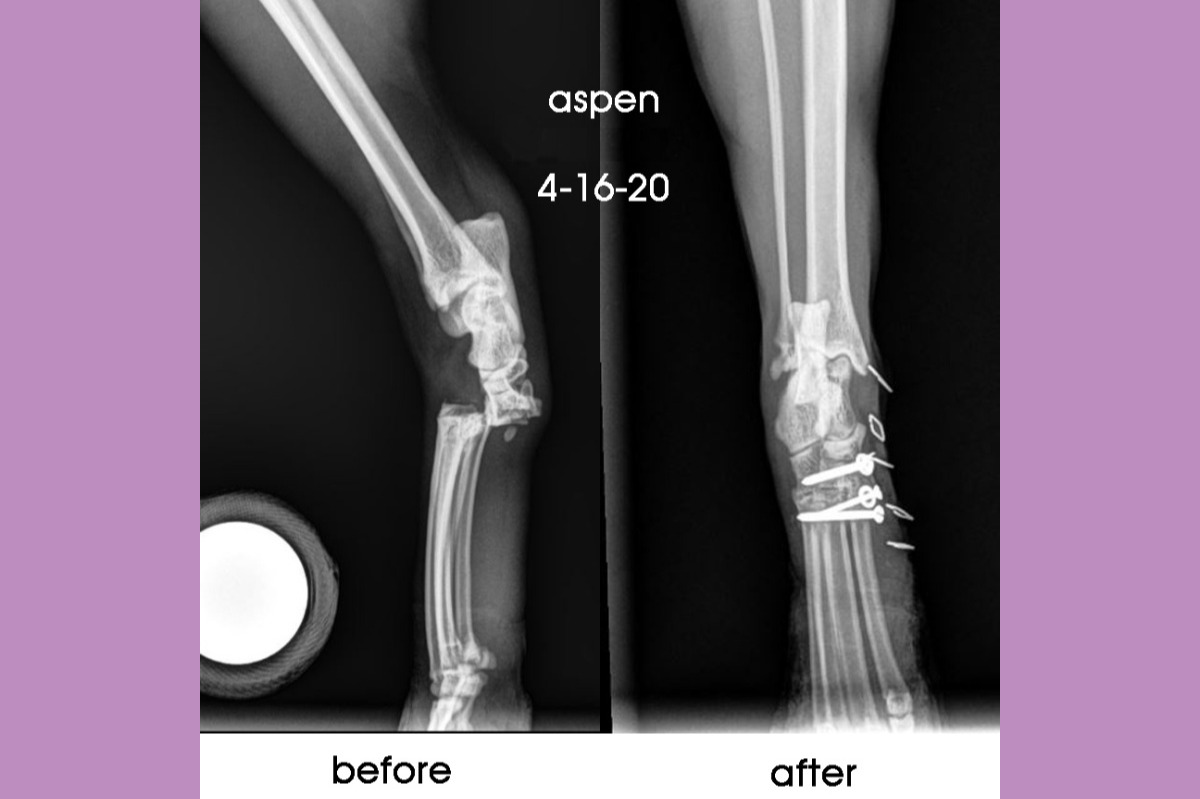

On April 16th, around 10am the surgeon called us with her plan. We listened in confusion and disbelief, we needed to approve her surgery without having seen an x-ray or met any doctor in person. Aspen's surgeon wanted to carve out all the cartilage from the four bones that connect to her ankle. Those four bones were all dislocated and some were broken. All of her ligaments were torn. She must have gotten her foot stuck in something behind our house, and it caught as she twisted and fell only two feet to the ground.

After surgery the doctor called us to explain what she saw. There was additional damage but she did not perform extensive repair beyond pinning the bones, removing cartilage, repairing one major ligament. She worried if she performed more work that there would be loss of blood to her foot and the foot could die. My heart dropped further into my stomach. They kept her overnight once more, and we sat at home dumbfounded and tried to comfort Maxwell and Fern, who could not find Aspen.

Monday April 20th Aspen had a successful bandage change and check up with her surgeon. This time at home we noticed some bloody drainage that came out the bottom of her cast, but were assured it was normal, and asked to keep checking her toes for temperature and look for a reaction to being touched.

Monday May 4th she got to see her surgeon again, who tested her toes and leg for movement, and believes her leg will be stable as long as healing keeps going well. Her incision was healed at this point and they removed the skin staples. Aspen has been shaking her foot a lot, and licking at the injury site, perhaps the skin is itchy and there is still some sore feelings around the broken bones.

I am deeply grateful to her surgeon and the team at our ER vet, who tended to Aspen with care and skill. During these uncertain times with the pandemic, I am grateful they are open and operating in the way they can while also keeping their staff and doctors safe. Now that we have had her 2.5 week checkup, and believe she is on the mend, perhaps my anxiety will ease a little. She will have an x-ray at 4 weeks to determine if her bones and the screws and implant are healing well. At best this will be a ten week healing period, without additional surgery, and she will be able to run and jump and climb and explore again.